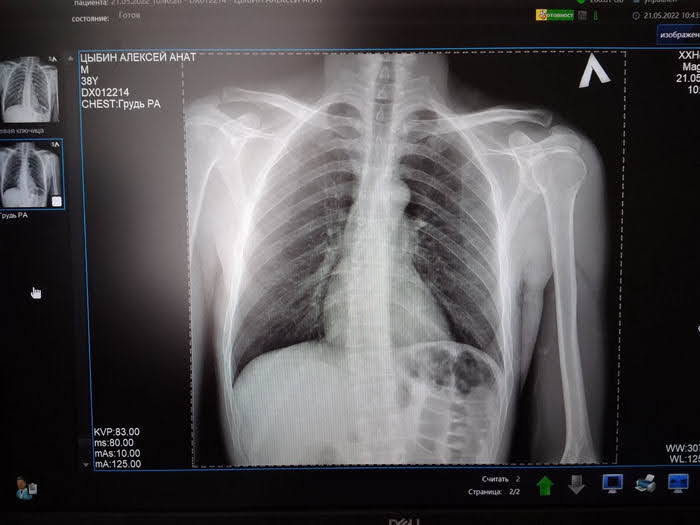

По предварительной информации, водитель автомобиля Mercedes остановился вторым рядом, а потом внезапно открыл дверь. В этот момент машину объезжал велосипедист, который врезался в открытую дверь.  В итоге велосипедист получил разрыв ключицы и гематомы. Ему предстоит операция и реабилитация.